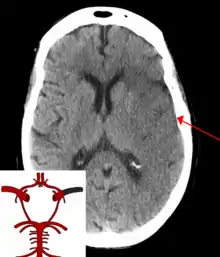

Stroke is a medical condition in which poor blood flow to the brain causes cell death.[5] There are two main types of stroke: ischemic, due to lack of blood flow, and hemorrhagic, due to bleeding.[5] Both cause parts of the brain to stop functioning properly.[5]

![]() | |

| CT scan of the brain showing a prior right-sided ischemic stroke from blockage of an artery. Changes on a CT may not be visible early on.[1] | |

The biggest risk factor for stroke is high blood pressure.[7] Other risk factors include high blood cholesterol, tobacco smoking, obesity, diabetes mellitus, a previous TIA, end-stage kidney disease, and atrial fibrillation.[2][7][8] Ischemic stroke is typically caused by blockage of a blood vessel, though there are also less common causes.[13][14][15] Hemorrhagic stroke is caused by either bleeding directly into the brain or into the space between the brain's membranes.[13][16] Bleeding may occur due to a ruptured brain aneurysm.[13] Diagnosis is typically based on a physical exam and supported by medical imaging such as a CT scan or MRI scan.[9] A CT scan can rule out bleeding, but may not necessarily rule out ischemia, which early on typically does not show up on a CT scan.[10] Other tests such as an electrocardiogram (ECG) and blood tests are done to determine risk factors and rule out other possible causes.[9] Low blood sugar may cause similar symptoms.[9]